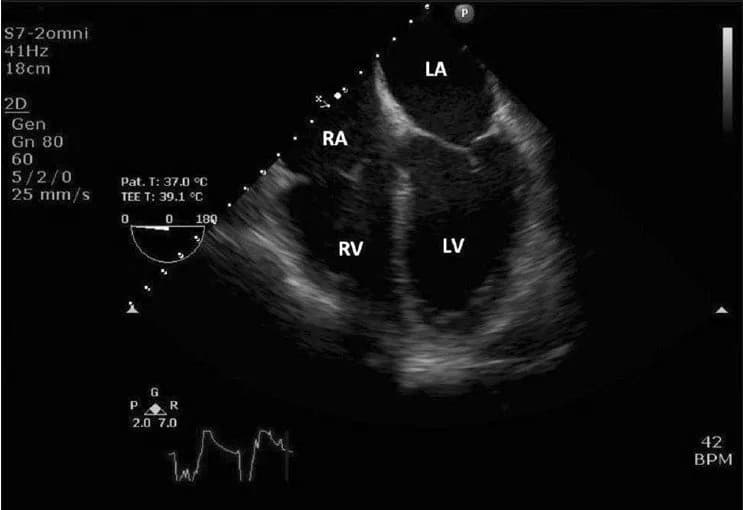

suy timnhồi máu cơ timbệnh tim mạchhở van timtăng áp động mạch phổi

Các bước thực hiện trước, trong và siêu âm tim

Siêu âm tim là kỹ thuật chẩn đoán hình ảnh tim mạch sử dụng sóng siêu âm để tạo ra hình ảnh tim. Phương pháp này giúp bá...

suy timtăng huyết ápnhồi máu cơ timbệnh van timkhó thở mãn tính

Quy trình siêu âm tim chuẩn hiện nay

Bài viết cung cấp thông tin chi tiết về siêu âm tim, một kỹ thuật chẩn đoán hình ảnh tim mạch quan trọng. Nội dung bao g...